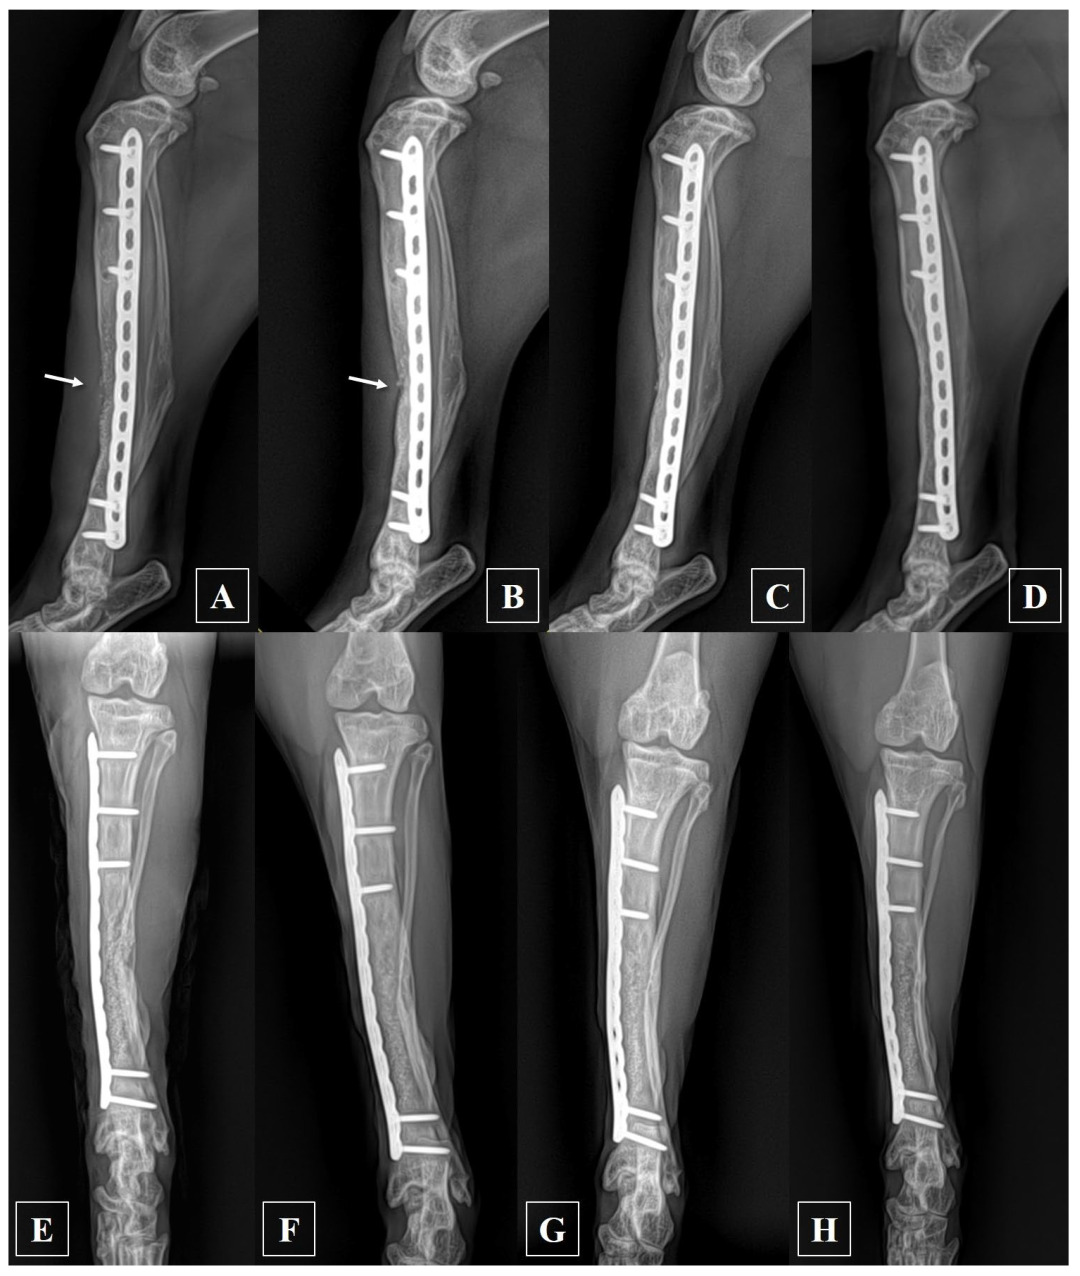

2.2. Anesthesia and Surgical Treatment

2.3. Postoperative Management and Prognosis